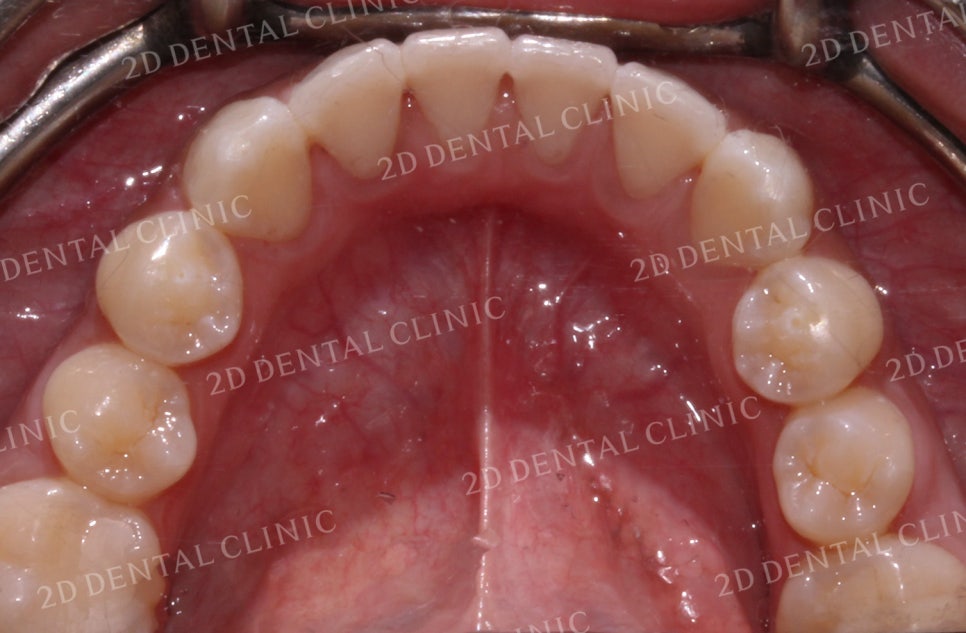

상악의 설측면 사진입니다.

교정 전 총생으로 인해

순측으로 틀어졌던 11번 치아가

교정 후 올바른 위치로

돌아오게 되었습니다.